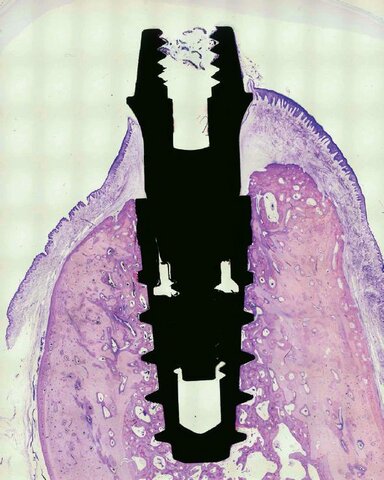

• Oseointegración de implante

Oseointegración de implante

Brånemark presenta al mundo odontológico la oseointegración y su implante de Titanio dando inicio a la era moderna de la implantología.